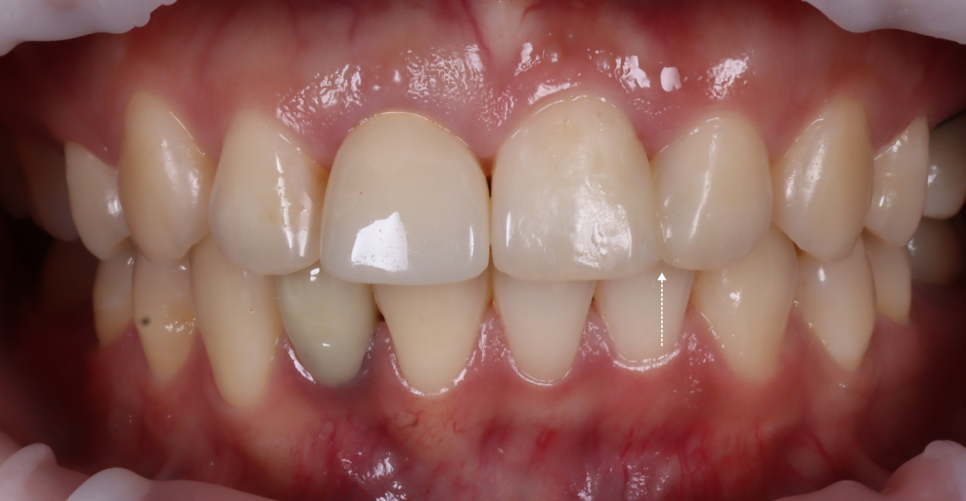

완성 후에는 치아 경계가 사라지고 자연 채광에서 봐도 거친 부분 없이 매끄럽게 보였어요.

촬영일 : 251023

이전의 각진 부분도 사라졌죠.

치료 후엔 잇몸과 치아 사이에 아주 얇은 ‘블랙트라이앵글’이 남았는데요.

왜 치아 사이에 공간이 생겼지?

라고 생각하실 수도 있는데요. 제가 일부로 만들어둔 것이랍니다.

자연스러운 곡선을 살리다 보면 잇몸이 완전히 닿지 않는 부분이 생겨요.

그걸 억지로 메우면 오히려 부자연스러워져요.

또, 치아 사이에 치실이 들어가지 않아 위생 관리가 어렵게 되어 충치도 잘 생기며, 잇몸에 염증도 잘 생기죠.

자연스러움을 위해 비울 줄도 알아야 합니다ㅎㅎ